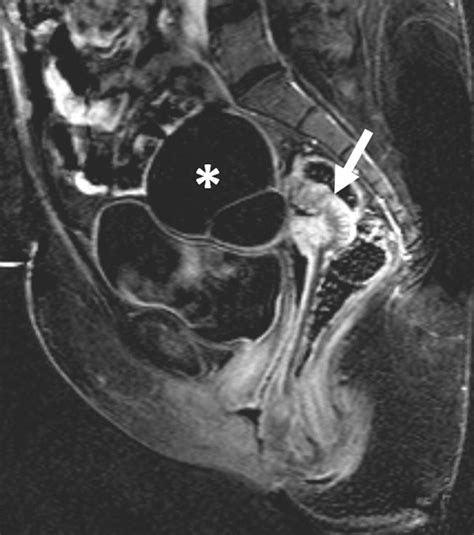

• Pelvic Structure: The pelvis is one of the most reliable indicators of sex on an X-ray. Female pelvises are generally wider and shallower, with a larger pelvic inlet and outlet. In contrast, male pelvises are narrower and deeper, with a smaller pelvic inlet and outlet.